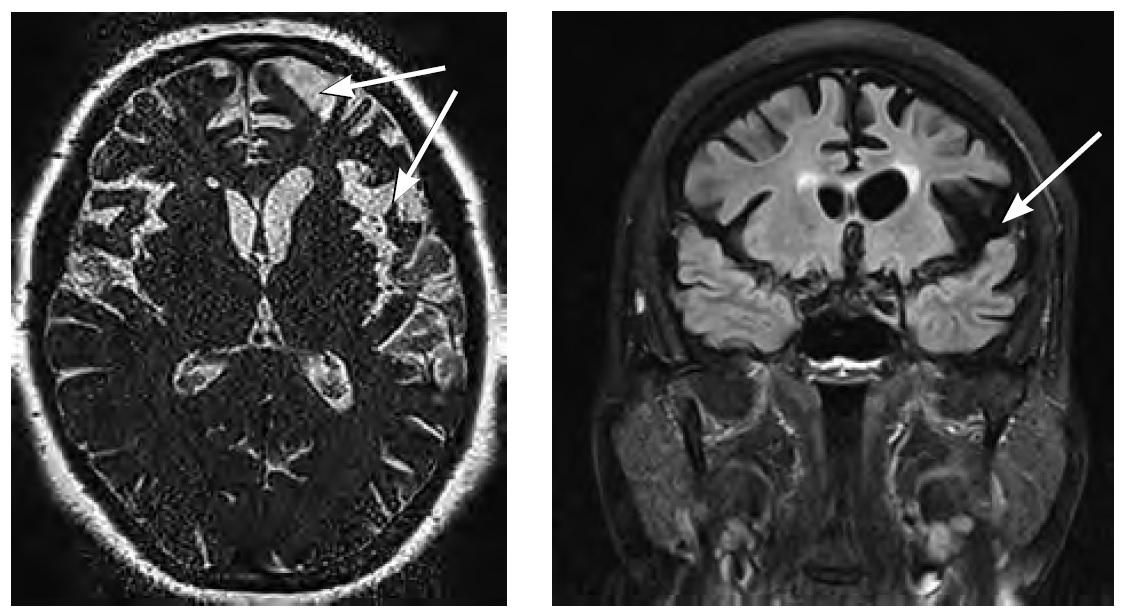

Ключевым нейрорадиологическим признаком является асимметричная атрофия, затрагивающая, главным образом, височно-теменные отделы доминантного полушария (рис. 4).

Рис. 4. МРТ головного мозга пациента с лППА в динамике: при первичном обращении (А), через 2 года наблюдения (В), через 3 года наблюдения (С). Выраженная асимметричная атрофия головного мозга с преимущественным вовлечением левой височной доли, затылочной доли. / Fig. 4. Brain MRI of a patient with lPPA over time: initial presentation (A), after 2 years of follow-up (B), after 3 years of follow-up (C). Significant asymmetrical brain atrophy, predominantly in the left temporal lobe and occipital lobe.